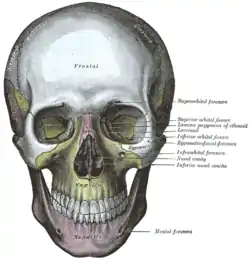

Visão lateral. Visão frontal.

Visão frontal. Parede medial da órbita esquerda.